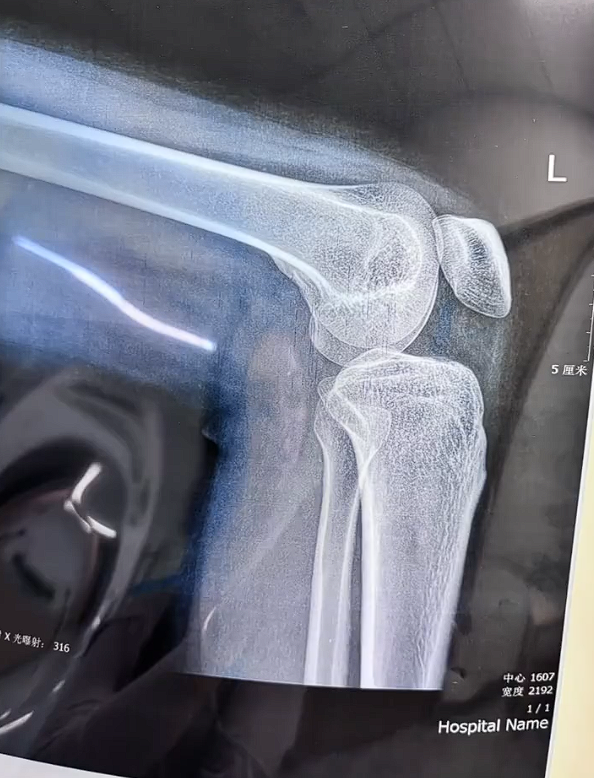

由于事发突然,加上所处的地方是个陡坡,女子被猴子蹬腿后失去了平衡直接向后摔倒在地,后续X光拍摄的片子显示已经发生骨折。